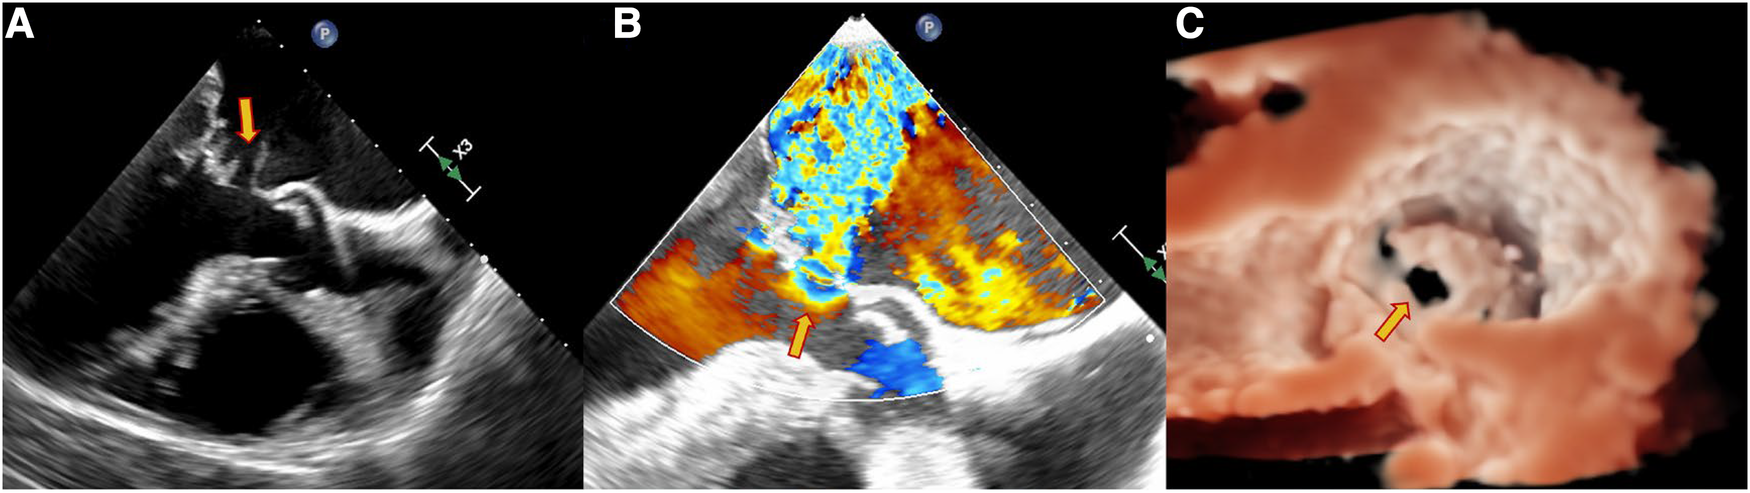

Figure 2

Echocardiography data of a 63-year-old male patient with dyspnea for 4 days. TEE showed the perforation of the MVA as pointed out by the yellow arrow. (A) Continuous interruption of the MVA wall. (B) Regurgitation from the MVA. (C) Continuous breaks on the MVA from a 3D view.